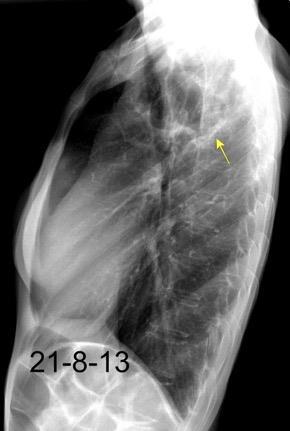

Nódulo en língula.

Cirugía de Ca .de mama hace 23 añosedema de brazo y ganglio en axila. ¡Metástasis!.

Ecanow JS et l. Axillary Staging of Breast Cancer: What the Radiologist Should Know. Radiographics 2013